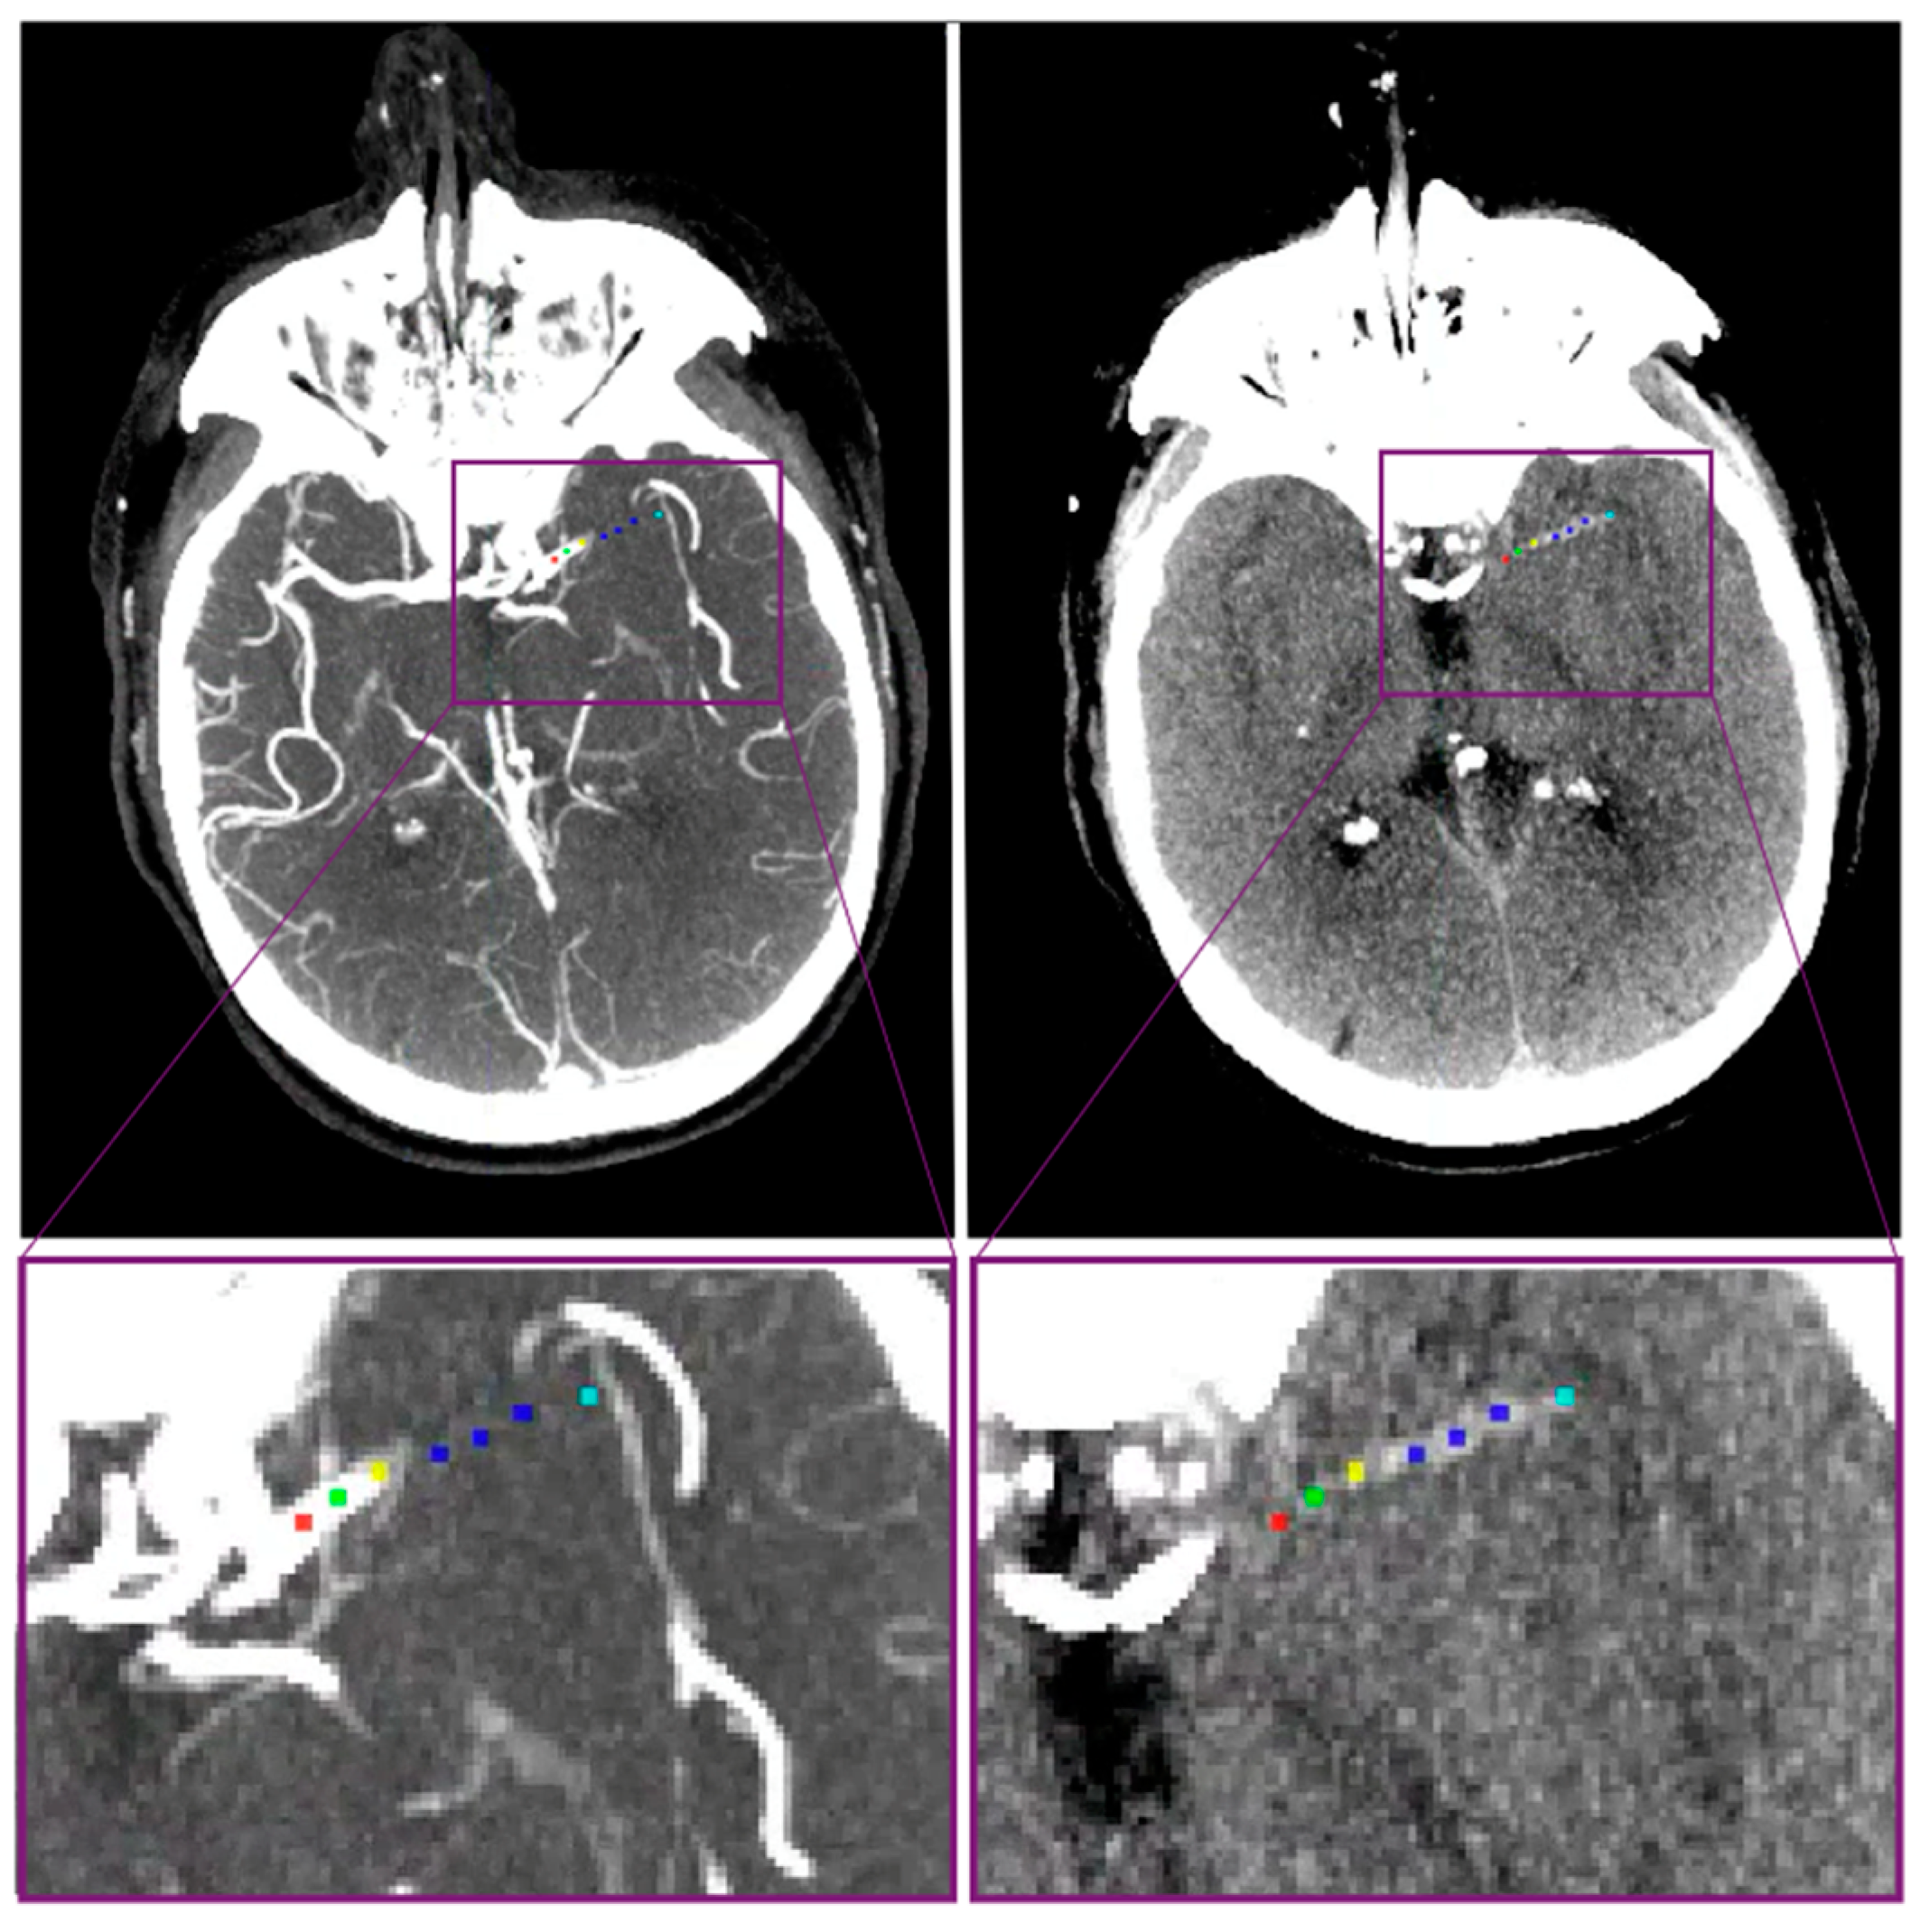

| DT | distance from intracranial carotid artery terminus to the thrombus |

| DT ι (mm)—median (IQR) | 23 (14–32) | 10 (0–21) | <0.01 |